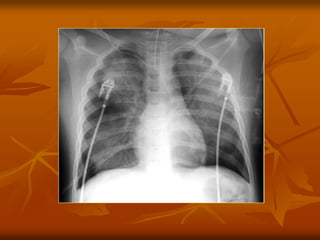

KHÍ AÛNH NOÄI PHEÁ QUAÛN

(AIR BRONCHOGRAM)

8